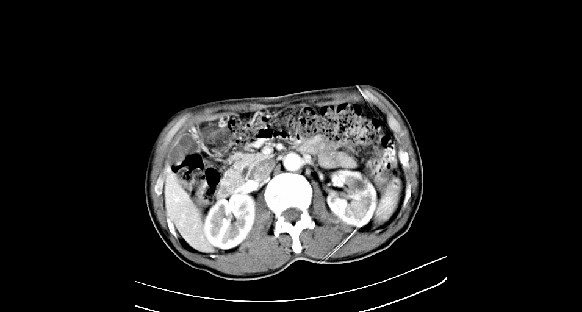

男性,70岁,体检b超发现左肾占位,请各位战友发表一下观点

左肾有两个病灶,且较大的病灶内可见点状钙化灶,增强扫描边缘也是呈渐进性强化,中央部分未见明显强化